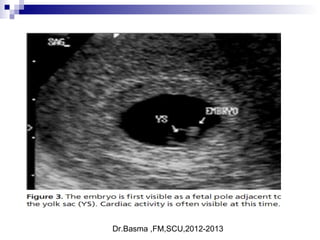

Intra uterine or ectopic pregnancy ?

5 week embryo and yolk sac

Dr.Basma ,FM,SCU,2012-2013